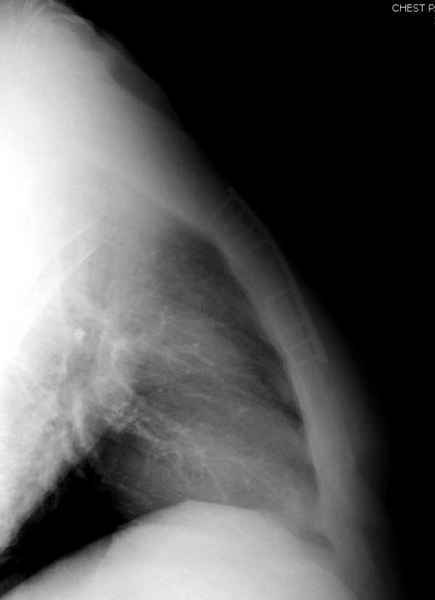

Юра, интересно, насколько такой остеосинтез контролирует степень репозиции, а то у меня имеются снимки девочки 11 лет, направленной ко мне на консультацию из одной из республик бывшего союза.

После торакальной операции, по-видимому, сильно натянули проволоку, и в результате получился захлест отломков в друг друга.

С такими продольными несращениями мне не приходилось иметь дело, поэтому направил в один из центральных институтов детской ортопедии России.

А простые посттравматические ложные суставы грудины приходилось оперировать с ограничителем сверла и с фиксацией 2.4 мм пластинами с угловой стабильностью.